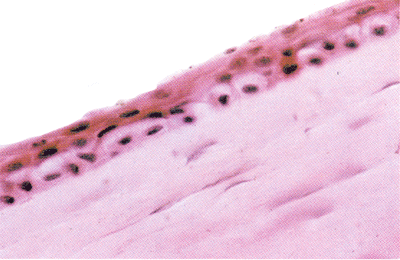

角膜水肿

此例为植人性虹膜囊肿继发青光眼。角膜水肿,上皮变薄,仅有2~3层。基底细胞呈水泡状。板层水肿变厚。固定细胞水肿,境界不清,染色淡。